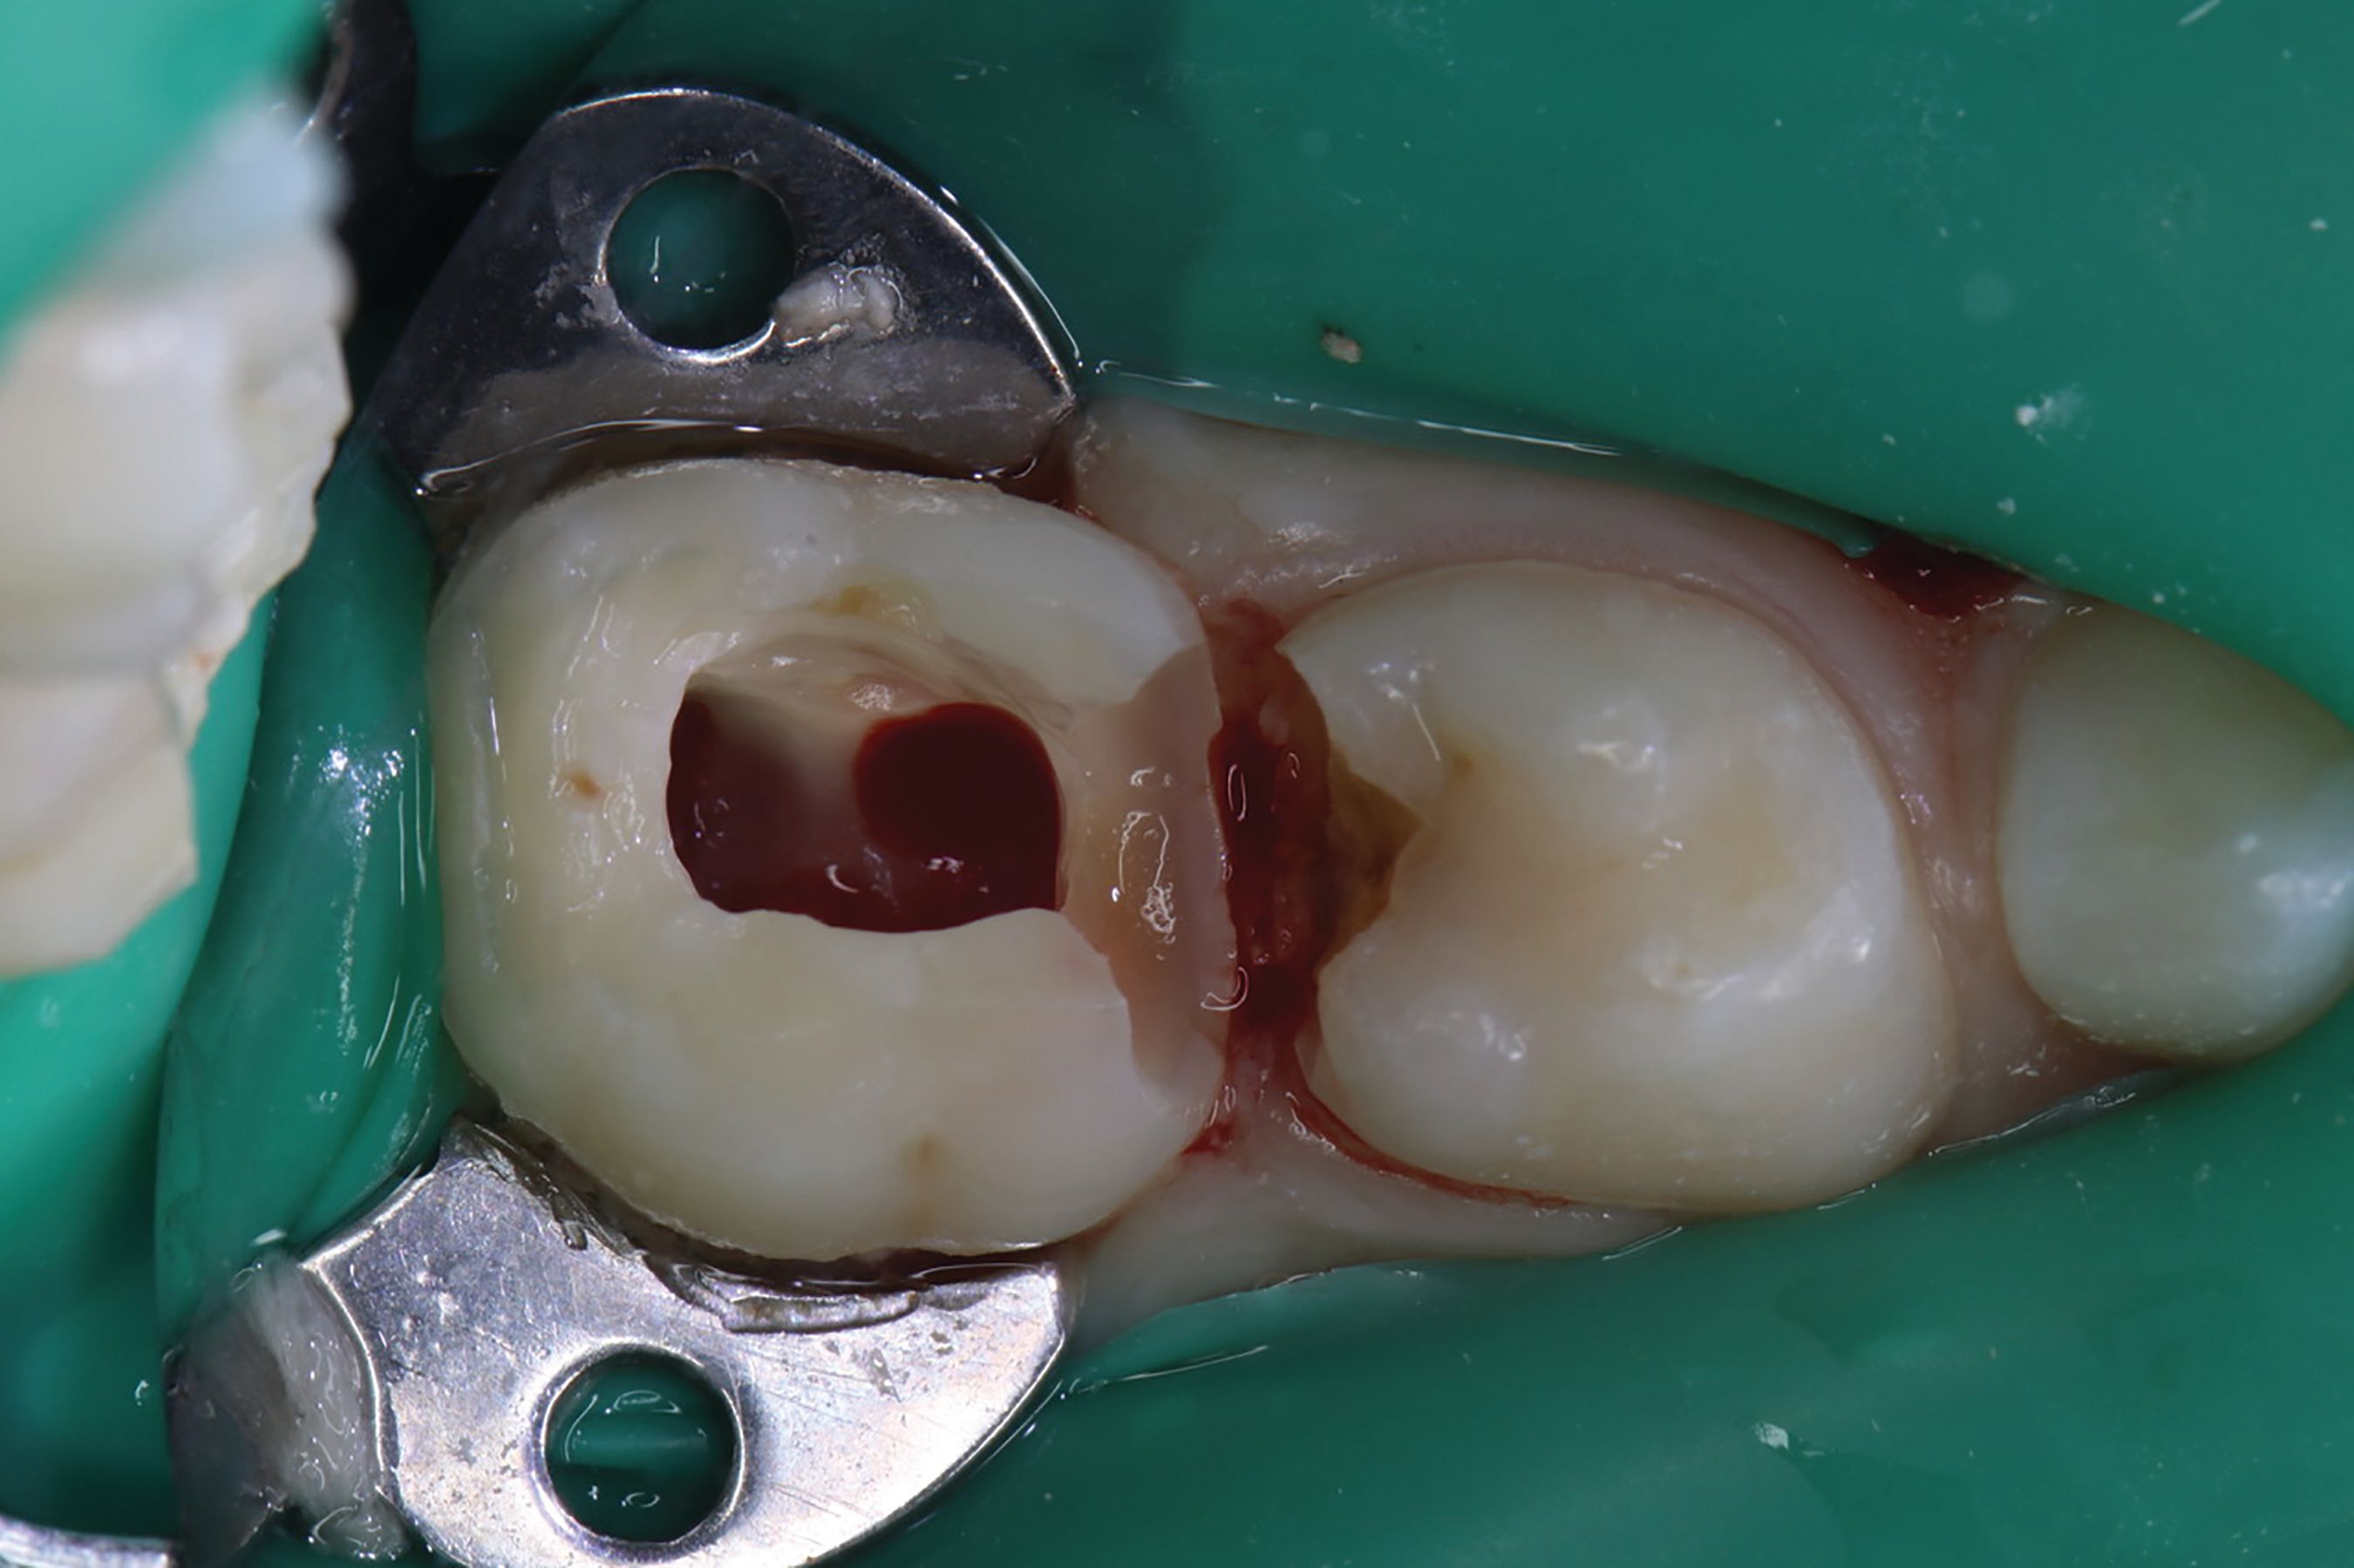

Amputation of coronal pulp chamber to the level of radicular pulp stumps was performed with NSK Dental slow speed large round bur #8, removing coronal pulp tissue with gentle upward motion (Fig. 2). Hemostasis is achieved with a saline-soaked sterile cotton pellet (Figs. 3-4). Figure 5 also illustrates hemostasis.

[ Figs. 1-9 ] Pre-operative view-primary second molar requiring pulpotomy procedure (Fig. 1). Amputation of coronal pulp chamber to level of radicular pulp stumps with NSK Dental’s slow speed large round bur #8, removing coronal pulp tissue with gentle upward motion (Fig. 2). Hemostasis achieved with saline-soaked sterile cotton pellet (Figs. 3 & 4). Hemostasis achieved (Fig. 5). Extrusion of TheraCal PT into pulp chamber, being sure to reach base of coronal pulp chamber with material and without voids or bubbles and light cure (Figs. 6 & 7). Cured TheraCal PT (Fig. 8). Full-coverage stainless-steel crown (Fig. 9).